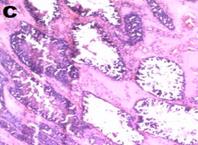

Histoarchitecture of the testes of treated animals showed mild to moderate atrophy and altered spermatogenesis (fig. 5). These were characterized by a reduction in the size of the seminiferous tubules and a decreased number of interstitial cells accompanied by spermatogenic arrest at high doses of the extract (fig. 5). The observations were in agreement with the reduced sperm numbers recorded.

Fig. 5: Photomicrograph (x40) showing histopathological profile of the testes of rat after 14 d treatment with varying doses of Carica papaya. A, B, C, D, E are control 10, 100, 300, 500 mg/kg of aqueous leaf extract of C. papaya respectively